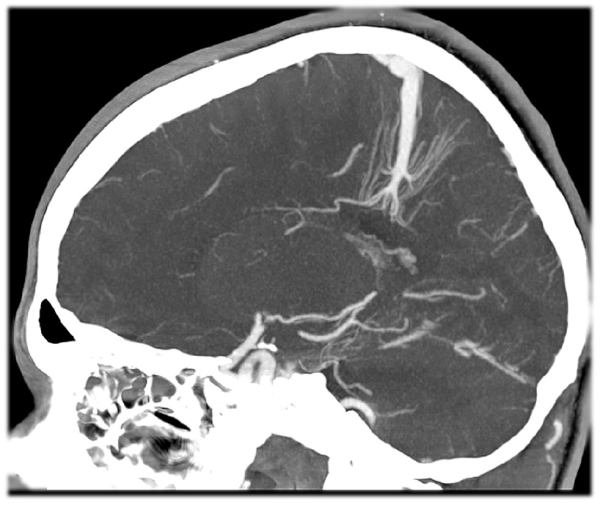

Для диагностики венозной ангиомы головного мозга используются различные методы исследования. Одним из них является компьютерная томография (КТ), которая позволяет получить рентгеновское изображение головного мозга с помощью компьютерной обработки данных. Другой распространенный метод — магнитно-резонансная томография (МРТ), которая создает детальные изображения головного мозга с использованием магнитных полей и радиоволн. Кроме того, может быть проведена ангиография, которая позволяет оценить состояние сосудов головного мозга с использованием рентгена и контрастного вещества.

| Компьютерная томография (КТ) | Получение рентгеновского изображения головного мозга с помощью компьютерной обработки данных. |

| Магнитно-резонансная томография (МРТ) | Создание детальных изображений головного мозга с использованием магнитных полей и радиоволн. |

| Ангиография | Оценка состояния сосудов головного мозга с использованием рентгена и контрастного вещества. |